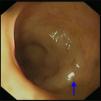

CaseA 65-year-old woman with an unremarkable medical history presented with intermittent dysphagia, which she reported had been causing a problem for approximately 1 year. The patient described a condition in which the passage of food took longer in the chest region, resulting in discomfort. Over time, the symptoms had worsened, and she had lost approximately 2kg in the previous 6 months. She finally sought medical attention in the outpatient department of our hospital. The initial physical examination findings were normal, except for an unexplained sinus tachycardia (an intermittent heartbeat of approximately 110 beats per minute). A subsequent esophagogram revealed a normal contour of the esophagus and the transit time was normal. Because the symptoms persisted and there was no sign of spontaneous regression, she underwent examination of the upper gastrointestinal tract by endoscopy. This did not provide any evidence of mucosal lesion, but the gastroenterologist did report an abnormal submucosal elevation in the lower third of the esophagus, approximately 2–3cm proximal to the esophagogastric junction (Fig. 1). Chest X-ray revealed a huge ovoid opacity in the right lower lung region adjacent to the mediastinum (Fig. 2). Computed tomographic scan indicated an enormous, low-density neoplasm in the posterior mediastinum, with a slight displacement of the esophagus (Fig. 3A), liver and inferior vena cava (Fig. 3B). Heart ultrasound revealed minimal right atrial and ventricular compression.